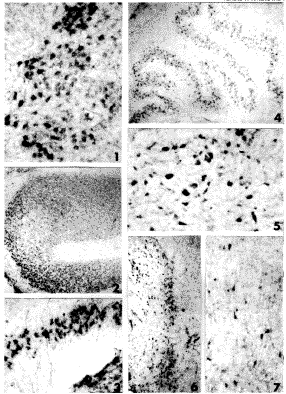

图1 第16周脊髓腹侧NOV mRNA神经元,细胞呈大多角形,杂交信号集中在细胞胞浆内,颜色较深 ×100

图2 第16周延髓下橄榄核NOV mRNA神经元多而密集 ×40

图3 第25周延髓下橄榄核内阳性细胞密度降低,细胞层数少而阳性信号强 ×40

图4 第28周延髓下橄榄核阳性细胞分布广泛 ×40

图5 第38周延髓薄束核NOV mRNA神经元明显分为大、中、小型,阳性信号强 ×100

图6 第32周纹状体内密集的NOV mRNA神经元,呈线状分布 ×40

图7 第38周顶叶皮质中NOV mRNA神经元位于皮质的Ⅴ、Ⅵ层,为突起明显的大锥体细胞 ×100